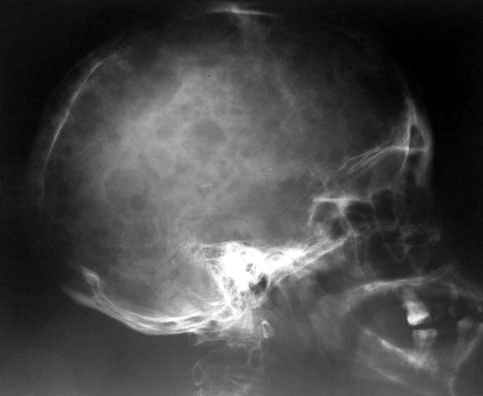

Уажаемые коллеги,представленные рентгенограмммы я показывал на нашем х-рей митинге - они были встречены с большим интересом.. Ну, ещё бы - я сам эту патологии встречал раза три за всю свою долгую жизнь:

VR> Кто шустрый - при какой патологии встречается так называемые <суставы Шарко>?

Сирингомиелия,

Травма спинного мозга

Опухоль

Т.н. нейрогенная артропатия бвает при диабете, периферических нейропатиях, заболеваниях спинного мозга... Как-то довелось вести больного с таким поражением тазобедренных суставов при третичном сифилисе.